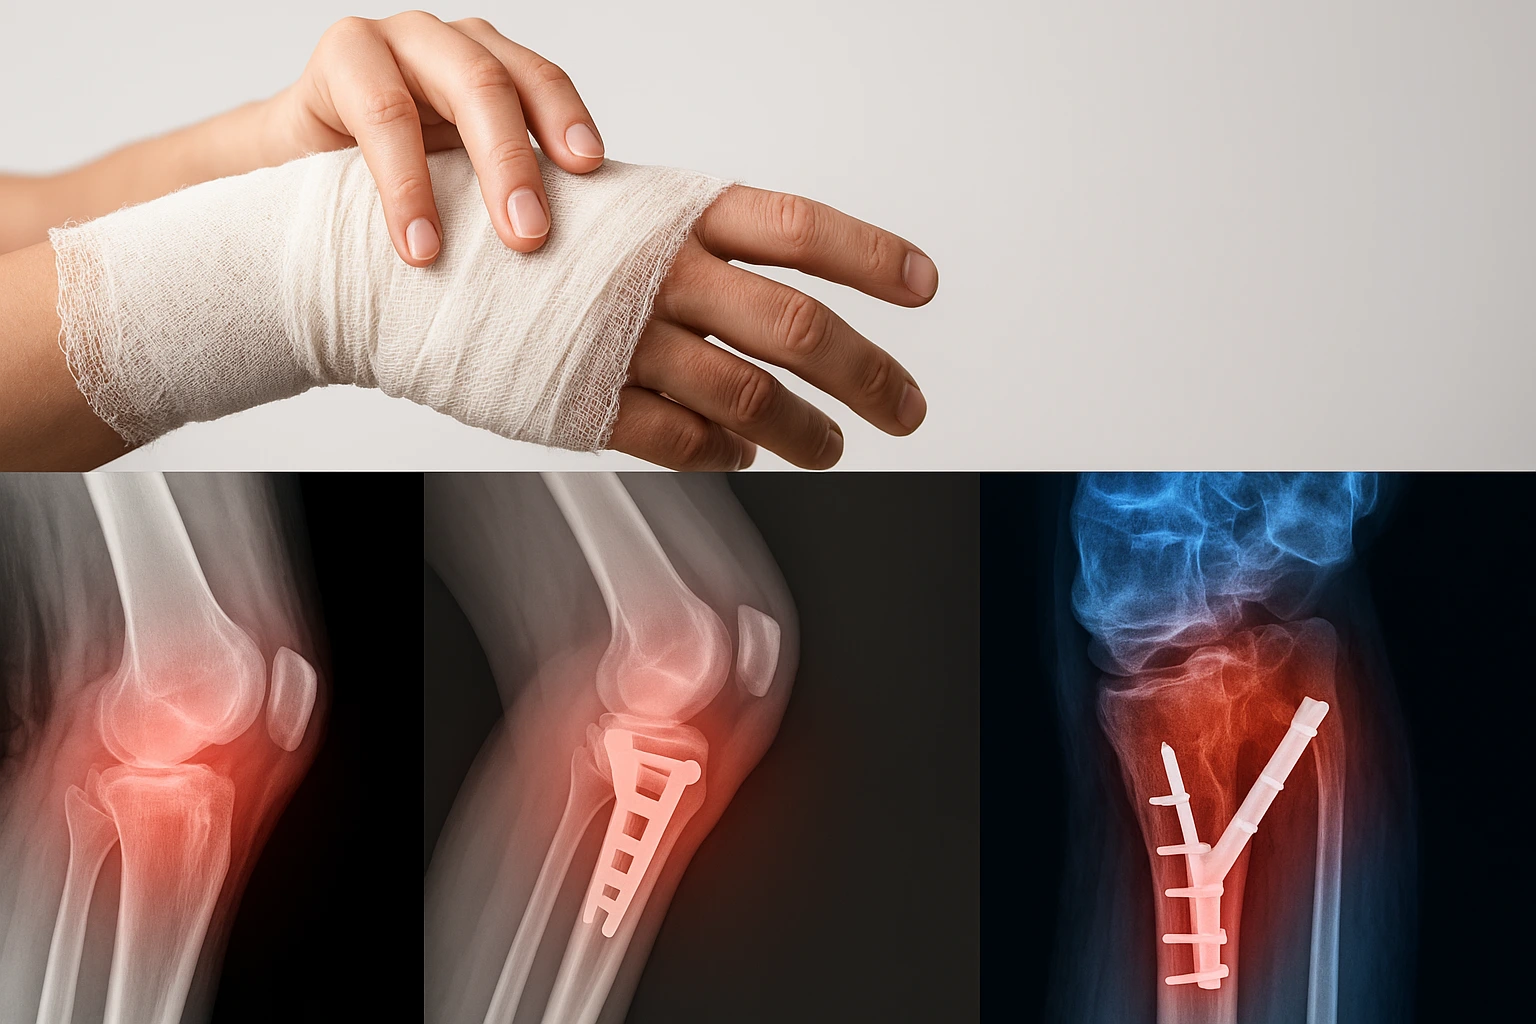

Fractures & Trauma

Prompt assessment and stabilisation of fractures and sprains.

• X-ray referral, casting & splinting

• Closed reduction for dislocations

• Operative fixation (ORIF) when indicated

• Rehab and return-to-work planning

Seek urgent care if: Open fracture / bleeding • Severe deformity • Blue or numb fingers/toes

What is it?

Injuries to bone and soft tissue ranging from sprains to displaced fractures.